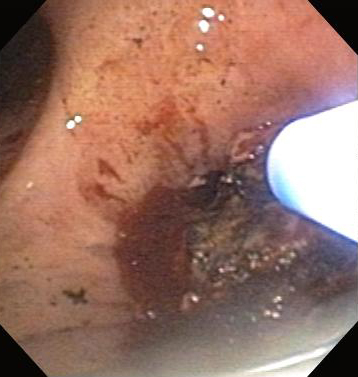

Post-lung transplant anastomotic bronchial stenosis: right mainstem anastomosis post-multimodal endoscopic therapy

From the collections of Jose Fernando Santacruz MD, FCCP, DAABIP and Erik Folch MD, MSc; used with permission